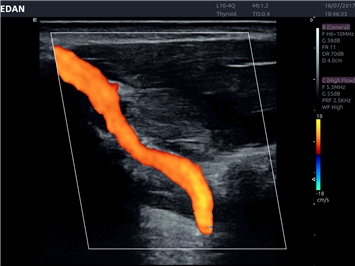

EDAN Acclarix LX4 представляет собой инновационную ультразвуковую систему, построенную на усовершенствованной платформе Acclarix. Сочетание высокого качества визуализации с интеллектуальным рабочим процессом делает эту систему оптимальным выбором для клиник, ценящих эффективность и экономичность.

• Сосудистой диагностики

Цветовой допплер:

Да

IMT (Intima Media thickness):